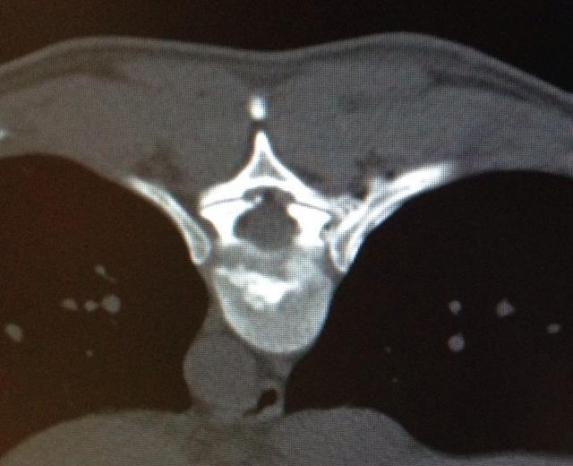

Wie immer in der Medizin ist die richtige Indikationsstellung wichtig für gute Ergebnisse. Nicht jeder Bandscheibenvorfall kann gelasert werden. So sollte der Faserring der Bandscheibe erhalten sein.

Bei einer Verödung der Bandscheibe werden in einer Sitzung auch die schmerzhaften Wirbelgelenke mitbehandelt.